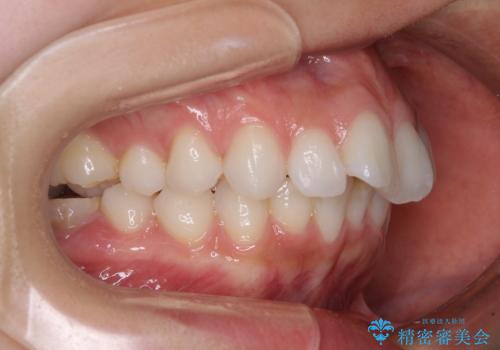

左右ともに奥歯の咬み合わせに問題があり、上顎臼歯が前方位にある状態で、結果として上顎前歯全体が前方位かつ叢生になっていました。

補助装置を用いて上顎歯列全体を後方に移動させ、下顎は左右で抜歯する小臼歯を変えることで、左右の咬み合わせをより理想的な位置となるように計画しました。